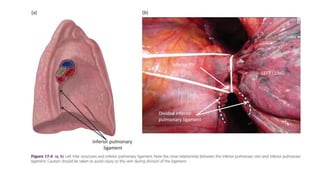

En resecciones lóbulo inferior  incide

ligamento pulmonar.

Resección lobar no anatómica. •~ Lesiones extensas; • Se aplica compresión digital/ clamp vascular – estructuras hiliares; • Disecan vasos; En resecciones lóbulo inferior  incide ligamento pulmonar. • Utilización engrapadora; antes de activación – dos suturas p/ fijación o fórceps Allis aplicadas en muñón  prevenir retracción; • Posteriormente línea de sutura – control sangrado o fuga aérea. • Cuidado desvascularización parénquima remanente.